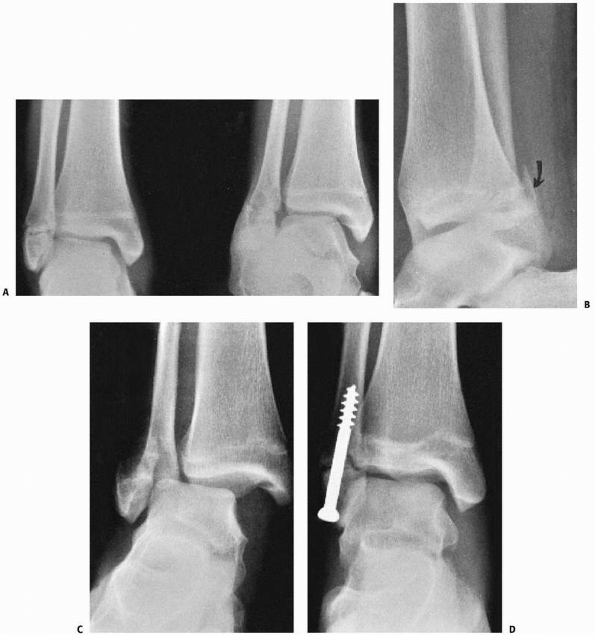

![]() |

FIGURE 26-31 A,B. Displaced distal tibial Salter-Harris type II fracture, with distal diaphyseal fibula fracture. C,D. Fracture treated with closed reduction and internal fixation.

reduction and cast immobilization. An above-knee nonweight-bearing cast

displacement after reduction, under anesthesia (Fig. 26-31).